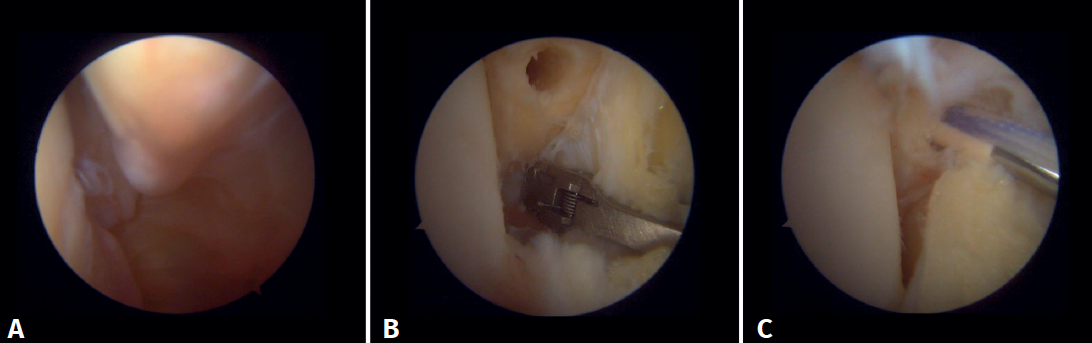

Arthroscopic evaluation of the syndesmosis

From the anteromedial portal we can directly visualize the distal fibers of the ATFL. Disinsertion of these fibers does not always result in instability of the syndesmosis, but it does require us to check it. In our experience, we prefer assessment of the coronal plane of the syndesmosis. We introduce the arthroscope into the tibiotalar joint directing the camera cranially. In this way we have a direct view of the distal tibiofibular joint. We then assess stability by attempting to insert the palpation probe into the joint. If it is possible to do so, we classify the syndesmosis injury as unstable (Figure 6A).

Arthroscopic evaluation of the deltoid ligament

There are multiple methods for assessing instability of the medial complex; using the anterior ankle portals it is possible to assess the stability of the deltoid ligament in its main plane of action, corresponding to the coronal plane. Chun et al.(20) described instability when it is possible to introduce an arthroscopic palpation probe into the medial tibiotalar space (Figure 6B). Vega et al.(21) reported that, in the majority of injuries, the most anterior portion of the deltoid ligament is detached from the medial malleolus, while its proximal insertions remain intact. In this situation, the arthroscopic palpation probe can be inserted between the medial wall of the internal malleolus and the deep fibers of the deltoid ligament.

Surgical technique: arthroscopic treatment of acute syndesmosis injuries

The technique should be performed using the conventional anteromedial and anterolateral portals. The anteromedial portal is used for visualization, while the anterolateral portal serves as the working portal. Once the tibiofibular space is visualized, the inflamed synovial component is resected with an arthroscopic shaver to facilitate reduction (Figure 7A). Then, under direct vision, we restore the tibiofibular space, carefully taking into account possible malrotation of the fibula, especially in Maisonneuve type fractures. For fibular reduction we use a Verbrugge clamp, which allows us to correct the rotation. In our experience, once the space has been cleaned and if the position is correct, it is infrequent to have to use a compression clamp between the tibia and fibula.

Once the desired reduction has been achieved, we visually check the position and temporarily fix it using a Kirschner pin.

For definitive fixation, the surgical options range between rigid fixation with screws and dynamic fixation. Screws have been the standard procedure for decades, but involve complications, such as loosening or rupture. Furthermore, some surgeons advocate their removal, with the inherent risk of recurrence of instability(27). Dynamic fixation was designed to overcome some of these problems by allowing a degree of physiological movement of the syndesmosis, facilitating early weight bearing, reducing the risk of rupture, and eliminating the need to remove the implant (Figure 7B).

Grassi et al., in a meta-analysis involving over 300 patients, demonstrated an overall decrease in the relative risk of complications (RR = 0.55, p = 0.003) with dynamic systems(28). Raeder et al., in a randomized trial of 97 patients contrasting screw fixation versus a dynamic system, reported a lower incidence of osteoarthritis with suture buttons of 65% versus 35% (p = 0.009) at 5 years(29). Suture button constructions afford a degree of micro-mobility, mimicking physiological mobility, which can promote ligament healing. Likewise, flexible implants are better able to tolerate an imperfect reduction, as a possible complication, even if arthroscopic control of the joint is performed.